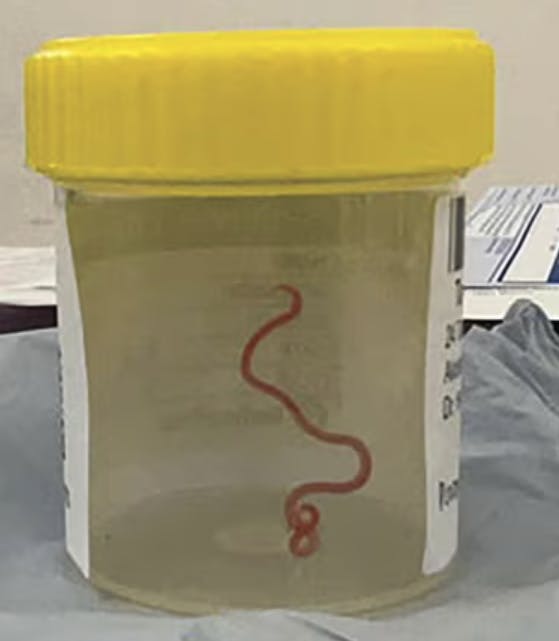

Både kirurgen og resten af teamet var selvsagt i chok over fundet, og man valgte hurtigt at sende den levende orm til videre analyse hos eksperter. De kunne hurtigt konkludere, at der var tale om en rundorm med det latinske navn Ophidascaris robertsi.

Den findes ofte i tæppepythoner, og det formodes, at kvinden har fået ormen ind i hjernen via netop denne type slange. Kvinden bor således i et område, der er kendt for at huse en hel del af netop denne type slanger. Kvinden husker dog ikke, at hun har været i direkte nærkontakt med en tæppepython, men lægerne mener, at rundormen kan have ligget i noget græs, som kvinden så har rørt ved.

Det er første gang nogensinde, at man har fundet en levende rundorm i en menneskehjerne. Kvinden er i bedring og er – naturligvis – blevet undersøgt for flere parasitter og orme.